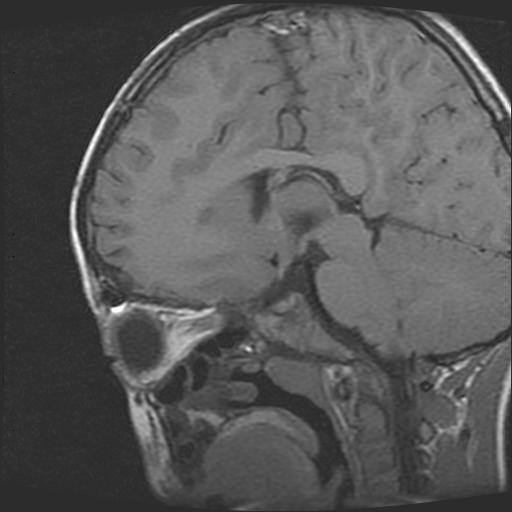

6岁小儿,左侧视神经瘤术后。现左侧视力减退。